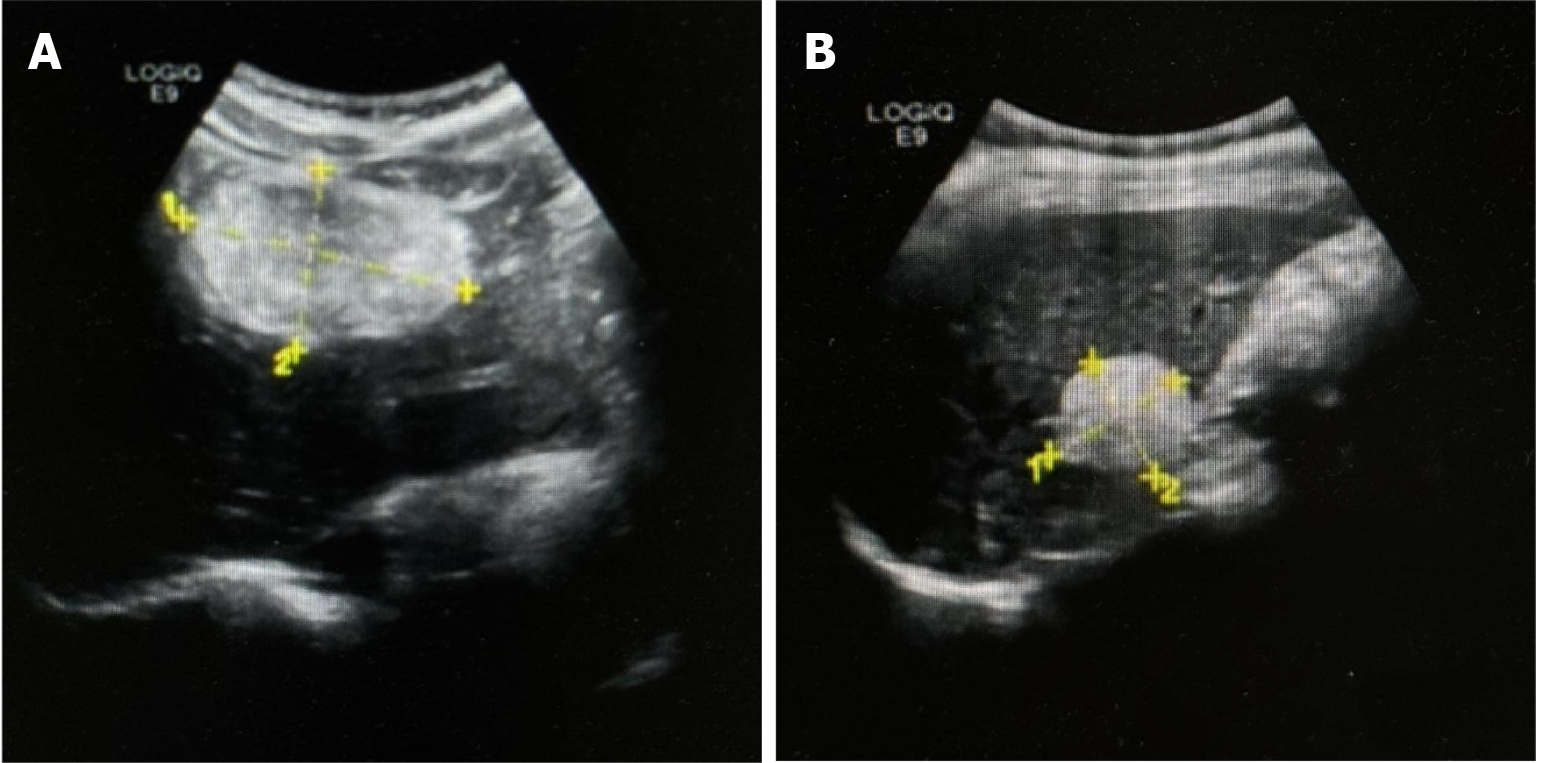

Five years prior, a well-defined, slightly hyperechoic lesion measuring approximately 23 mm × 15 mm was discovered via abdominal ultrasound in segment S3 of the left lateral hepatic lobe. An additional lesion, measuring approximately 48 mm × 44 mm, was detected in the anterior segment of the right hepatic lobe. These findings were considered consistent with hepatic hemangiomas, and routine imaging follow-up was recommended. A follow-up ultrasound performed 3 months prior at a local hospital identified two hyperechoic lesions in the liver parenchyma, measuring 55 mm × 38 mm and 29 mm × 31 mm, respectively. Both lesions remained well-circumscribed, and hepatic hemangioma was again considered likely; continuing imaging surveillance was advised. Due to progressive enlargement of the lesions on serial imaging, the patient presented to our hospital for further evaluation and management.

Ultrasound demonstrated a slightly hyperechoic lesion measuring approximately 71 mm × 49 mm in the left hepatic lobe and an additional lesion of approximately 33 mm × 32 mm in the right lobe, both with sharply defined margins. These sonogram findings were consistent with hepatic hemangiomas (Figure 1). Contrast-enhanced computed tomography (CT) of the upper abdomen revealed mass lesions in hepatic segments S3 and S7, with the larger one in the left lobe measuring approximately 61 mm × 44 mm and showing heterogeneous density. In the arterial phase, the lesion exhibited pronounced heterogeneous enhancement, with visible intratumoral vasculature and adjacent vessel dilation. The lesion became isodense during the portal venous and delayed phases. These radiologic findings were consistent with a possible diagnosis of AML (Figure 2).